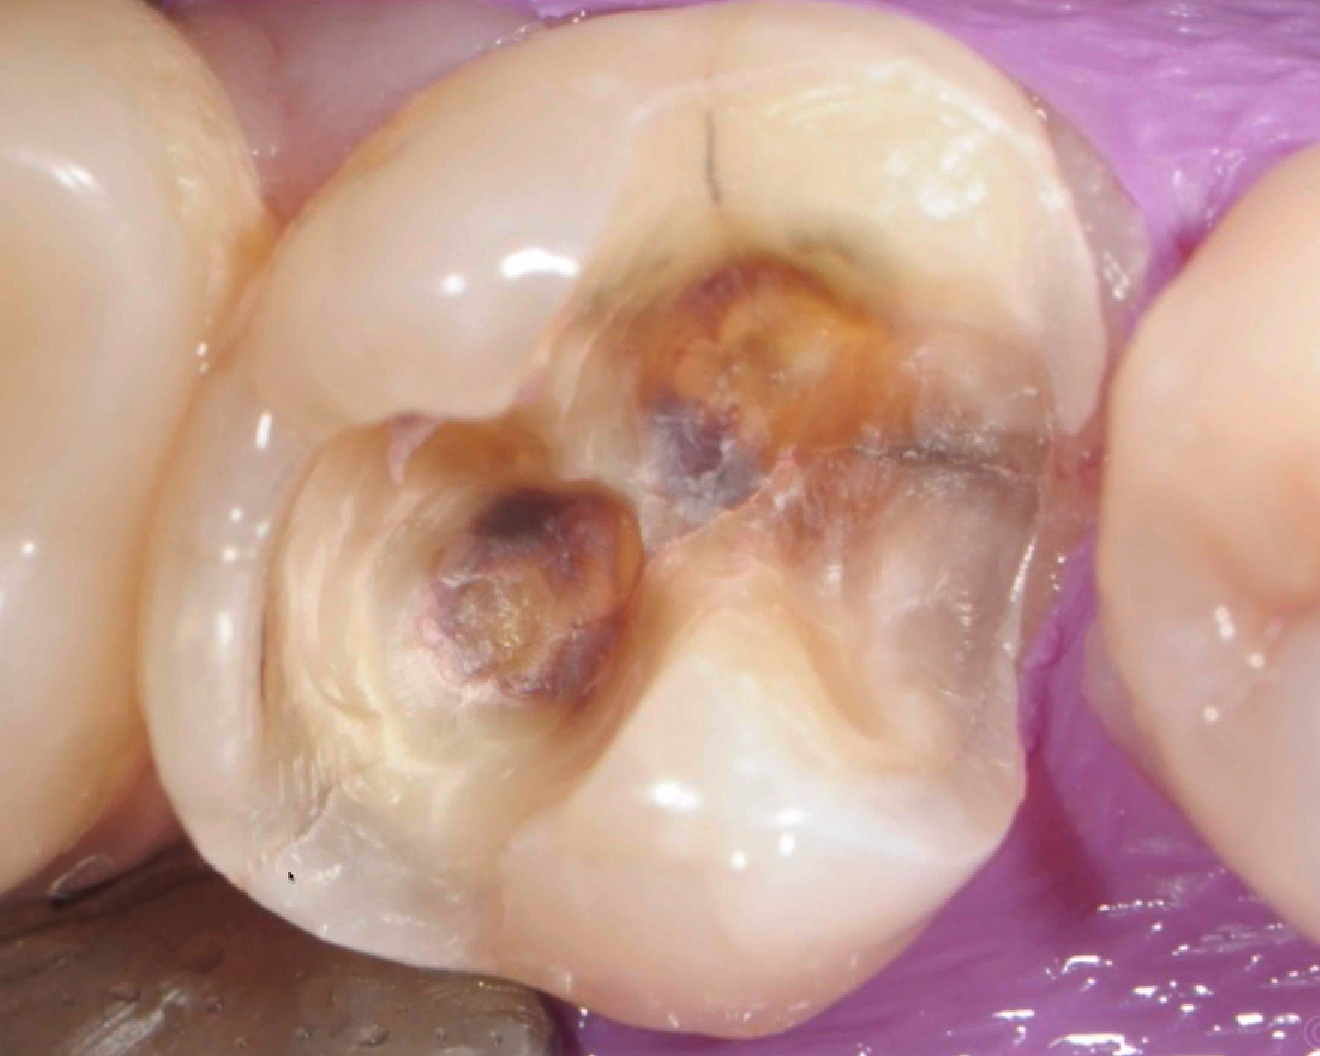

Take a look at the old silver filling in this picture. If you look carefully, you will see minor crack lines that go through the tooth from one end to the other. This tooth is breaking and this crack is running through the existing silver filling. However, there are absolutely no symptoms! Unfortunately, the implications of these crack indicate a high risk of breakage and extraction needed in the future. By seeing the crack lines early, we have an opportunity to save this tooth by placing a crown.

Fillings are great in sealing a tooth with a cavity, however, they do not protect the tooth from breaking. This is why we recommend crowns for teeth that are at high risk. Typically these teeth are back molars with major biting force, root canal teeth, and teeth with large fillings without good structural support.